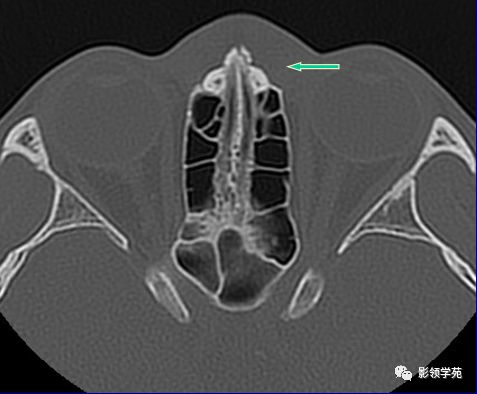

右侧鼻骨骨折

左上颌骨额突骨折

双侧鼻骨骨折

双侧上颌骨额突骨折